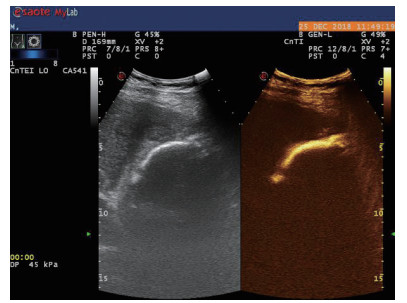

1.3 手术过程 1.3.1术前经肘静脉超声造影:行PTGBD前半h经肘静脉快速团注SonoVuel 5 mL,在对比脉冲序列造影成像模式下进行观察,根据不同组织造影剂凝聚的时间及浓度差异,判断胆囊周围组织黏连程度、胆囊壁完整程度(图 1),如出现胆囊壁造影剂充盈缺损(图 2、3),则考虑胆囊壁坏死或穿孔,根据静脉造影情况选择合适的置管入路,避开胆囊穿孔的部位及黏连组织。

| 图 1 经肘静脉超声造影胆囊图像,造影图(左),二维超声图(右) |

超声造影是利用超声造影剂微泡(本组应用的是声诺维超声造影剂微泡)在低机械指数声波照射下发生共振,产生线性及非线性谐波回声信号,形成造影增强图像的技术,是近年来新兴的超声技术,具有实时、可连续观察、无辐射、可重复性好、毒不良反应少等优势,为临床提供了全新的诊疗手段[14]。经肘静脉注入的标准配置超声造影剂是一种血池造影剂,可以反映组织的血流灌注情况同时亦被广泛应用于肝、脾、肾等实质性脏器破裂的诊断,其诊断的敏感性及特异性均明显优于二维超声,且与增强CT有较好的一致性[15-16]。本组病例术前经肘静脉注入标准配置造影剂后,胆囊壁均显影增强,胆囊穿孔及周边积液处表现为造影无充盈区,穿刺置管后再次静脉路超声造影,迅速发现术后出血部位且可敏感评估是否为活动性出血(经手术证实)。除1例因活动性出血中转腹腔镜手术外,其余32例置管成功后经引流管口注入稀释造影剂20 mL(1:200稀释),评价引流管位置、引流范围及是否出现胆汁外漏取得良好效果,所有引流导管均能够清晰显示引流导管置入路径、引流管形态及引流范围,引流管置入恰当者,头端位于胆囊内,全管显影清晰,造影剂弥散区域与胆囊大小吻合; 置管后胆汁漏出者,可见造影剂沿引流管周边渗出[17-18],本组中3例出现造影剂外渗,其中两例渗出范围局限于胆囊床附近,未渗出至游离腹腔,患者腹痛症状稍有加剧,经胆囊减压及对症处理后好转,其中1例见造影剂渗出至肝肾间隙,患者腹痛症状加剧明显,考虑置管位置不当,余行急诊腹腔镜手术治疗,术中证实为系膜胆囊,且可见引流管侧孔部分外露。笔者的经验是,术前选择静脉路超声造影有助于对胆囊情况的评估及穿刺点的选择,术中正确选择穿刺针的入路有利于提高穿刺引流的成功率。首先是胆囊穿刺部位的选择应选择在靠近胆囊颈侧,此处胆囊位置比较固定,受体位影响较小,且胆囊床结缔组织较为固定,有助于将漏出胆汁包裹局限,其次是进针方向与胆囊床尽可能保持垂直,减少进针位置的偏移,同时置管成功后应即刻尽量抽尽胆囊内的感染性胆汁,生理盐水冲洗后行经引流管稀释超声造影有助于判断置管位置、引流范围及是否出现胆汁漏出,减少不必要的并发症发生率。穿刺引流后可以根据患者的营养状况待窦道形成稳定后择期拔除引流导管。对全身情况改善适合手术治疗且有手术意愿者可以考虑择期胆囊切除术。